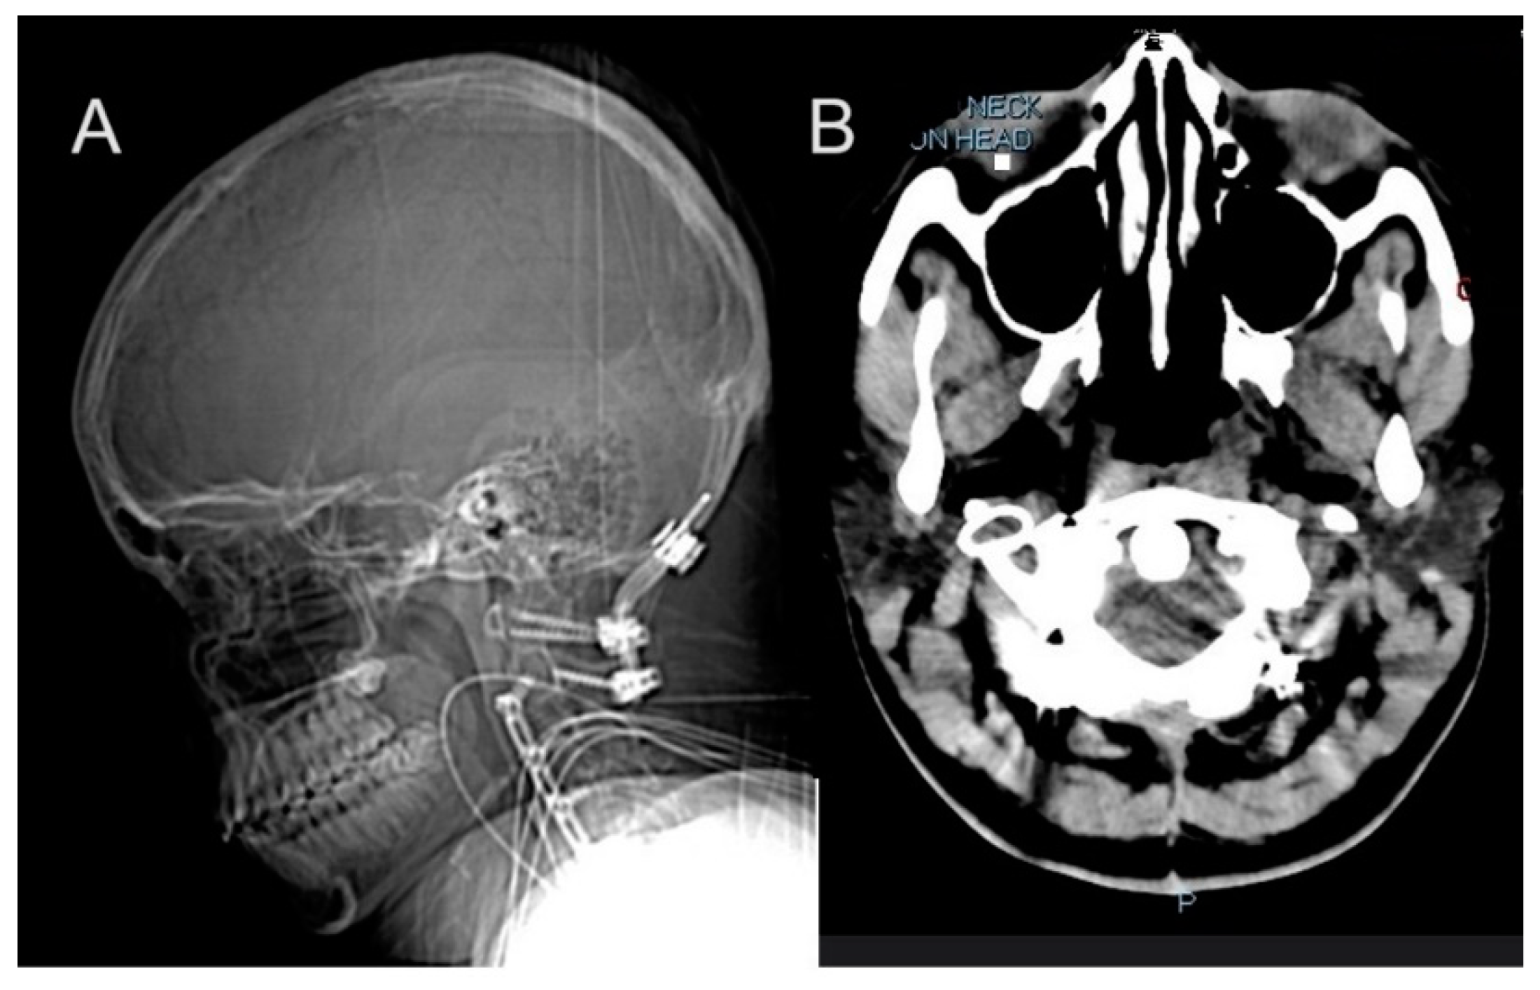

2.2.2. Progressive Spinal and Vascular Complications

2.3.2. Central Nervous System Findings